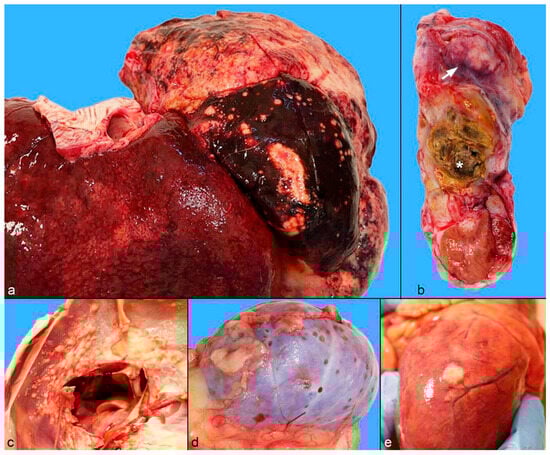

2.2. Gross Pathology